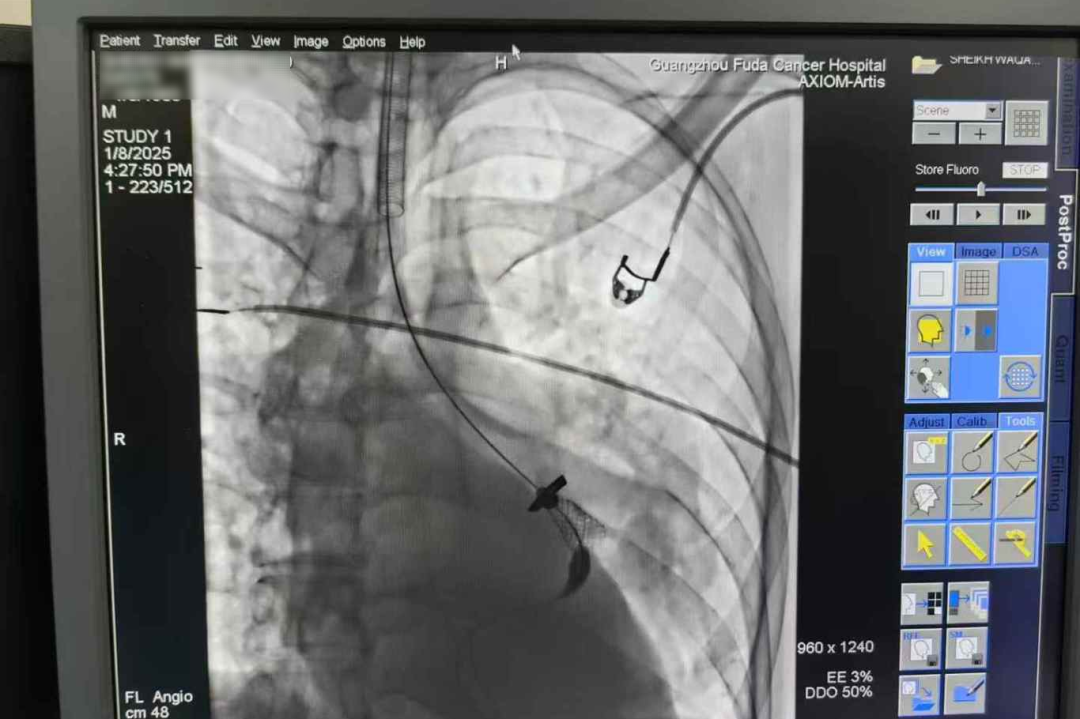

上面这位患者来自巴基斯坦,双肺多发转移病灶,经过化疗、靶向药治疗后仍有部分转移。由于病灶较大,挤压并粘连双侧支气管、左心房、双下肺静脉、胸主动脉、食管,以至于该患者气道复杂、狭窄,呼吸困难。我们介入团队在内镜联合DSA引导下,进行气道内肿瘤消融+支架植入术,反复电切、止血、消融、疏通的同时植入支架,历经近三个小时终于打通了气道,为进一步治疗争取了时间。

其中,支架置入是指通过导管将支架送至气管内的狭窄部位,张开后起到支撑管壁,维持气道通畅的作用,从而达到改善呼吸功能的目的,主要针对恶性肿瘤引起的气管支气管狭窄进行姑息治疗,以迅速解除患者呼吸困难的症状,为后续治疗创造条件和机会。

这是呼吸介入技术中难度风险系数最高的手术之一,其优势在于创伤小,可帮助患者很好地解决气管狭窄引起的呼吸急促、气管食管瘘继发吸入性肺炎等问题,起到持续扩张气道的作用,在上述所有方法均不能达到通畅气道的目的时可选用。

我们介入科团队在这方面有成熟和丰富的诊疗经验。术中麻醉医生全程配合,支气管镜联合DSA在恶性气道狭窄中的活检、吸痰、止血、冷热消融及支架置入,技术成功率100%,安全且疗效满意,为患者点亮生命之光。